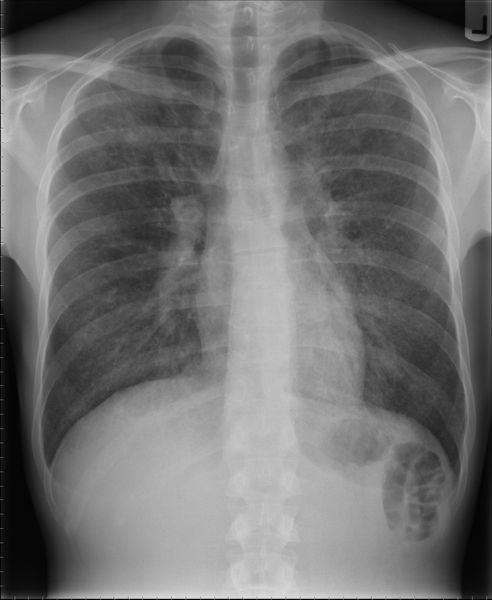

Besonders für ältere und geschwächte Menschen kann eine Lungenentzündung tödlich verlaufen. Es gibt allerdings Möglichkeiten zur Vorbeugung. So entwickeln Potsdamer Forscher einen Impfstoff gegen Pneumokokken, der Infektionen verhindern soll – und damit auch gegen Pneumonie schützen würde.

Quelle: Samir, https://de.wikipedia.org/wiki/Lungenentz%C3%BCndung#/media/File:PCP_CAP_CXR.jpg (CC BY-SA 3.0) (Bild: Samir, (CC BY-SA 3.0))